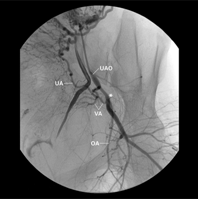

Thuyên tắc động mạch tử cung (UAE)

Năm 1990, các nước Âu-Mỹ tiến hành nghiên cứu và ứng dụng kỹ thuật thuyên tắc động mạch tử cung để điều trị u xơ tử cung. Đây là phương pháp an toàn, hiệu quả, chi phí thấp mà còn ưu điểm hơn so với phương pháp phẫu thuật là người bệnh hồi phục sức khỏe nhanh, thời gian nằm viện ngắn, nhất là tránh những sang thương tâm lý do việc phẫu thuật cắt tử cung gây ra. Hiện nay kỹ thuật thuyên tắc động mạch tử cung còn được ứng dụng rất hiệu quả trong những trường hợp chảy máu trong sản phụ khoa.

Một nghiên cứu đoàn hệ tiền cứu so sánh điều trị với UAE với những phương pháp điều trị khác trong BHSS. 10/13 trường hợp điều trị với UAE là thành công. Trong số 11 trường hợp phải phẫu thuật chỉ có 2 trường hợp ở nhóm UAE. Mười tám báo cáo hàng loạt ca và mười báo cáo trường hợp bệnh về UAE trong điều trị BHSS đã được xuất bản trên thế giới với tổng cộng 340 bệnh nhân với tỉ lệ thành công từ 82% đến 100%.

WHO khuyến cáo, nếu các can thiệp khác không hiệu quả và phương tiện tại chỗ sẵn có UAE có thể là lựa chọn để điều trị BHSS do đờ tử cung (mức độ khuyến cáo yếu). Tuy nhiên UAE đòi hỏi đầu tư quan trọng, chi phí của điều trị, máy móc và đào tạo nhân sự.